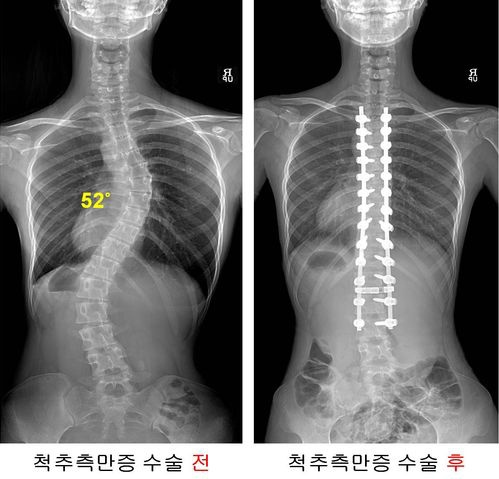

¼­¿ï¾Æ»êº´¿ø ôÃßÃø¸¸Áõ¼¾ÅÍ´Â Áö³­ 2015³â °³¼Ò 6³â¸¸¿¡ ôÃßÃþ¸¸Áõ¼ö¼ú 1õ·Ê¸¦ ´Þ¼ºÇß´Ù.

¼¼°è 12À§ Á¤Çü¿Ü°ú ºÐ¾ß, Áúȯ ¼¼ºÐÈ­ Àü¹®Áø·á

¼­¿ï¾Æ»êº´¿ø Á¤Çü¿Ü°ú´Â ¼¼ºÐÈ­µÈ Ä¡·á·Î ȯÀÚµéÀÇ ³ôÀº È£ÀÀÀ» ¾ò°í ÀÖ´Ù.

°æÃß, ¿äÃß, ¹«¸­, ¾î±ú ¹× ÆÈ²ÞÄ¡ Áúȯ, »À¾Ï, ¼öºÎÁúȯ, ¹ß°ú ¹ß¸ñ Áúȯ µîÀ» ¼¼ºÐÈ­ÇØ Àü¹® Áø·á¸¦ ½ÃÇàÇϰí ÀÖ´Ù.

2009³â °³¼ÒÇÑ Ã´ÃßÃø¸¸Áõ¼¾ÅÍ´Â Á¤Çü¿Ü°ú¸¦ Áß½ÉÀ¸·Î ½Å°æ¿Ü°ú, ½Å°æ°ú, ÀçȰÀÇÇаú, ¿µ»óÀÇÇаú, ½ºÆ÷Ã÷ÀÇÇм¾ÅͰ¡ ÇùÁøÇØ Ã´ÃßÃø¸¸Áõ ȯÀÚ¿¡°Ô ÃÖÀûÀÇ Ä¡·á¸¦ Á¦°øÇϰí ÀÖ´Ù.

1990³â SÀÚ ÇüÅ·Π±¸ºÎ·¯Áø ôÃ߸¦ ¹Ù·Î ¼¼¿öÁִ ôÃßÃø¸¸Áõ ¼ö¼ú¿¡ ¼º°øÇÑ ÈÄ Áö±Ý±îÁö 1300·Ê ÀÌ»óÀ» ½ÃÇàÇß´Ù.

2015³â ÀÌÈÄ¿¡´Â ¸Å³â 180°Ç ÀÌ»óÀÇ Ã´ÃßÃø¸¸Áõ ¼ö¼úÀ» ÁøÇàÇϰí ÀÖÀ¸¸ç ¼ö¼ú ÈÄ ½Å°æ¼Õ»ó ȯÀÚ°¡ °ÅÀÇ ¹ß»ýÇÏÁö ¾Ê¾Æ ¾ÈÀü¼ºµµ ÀÔÁõÇß´Ù.